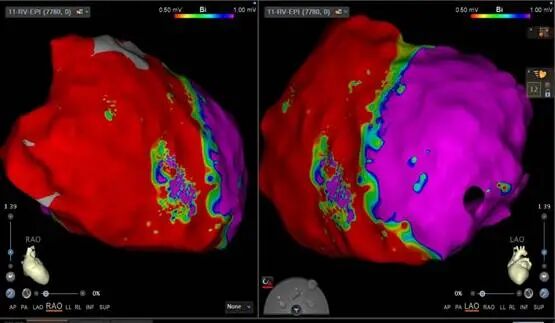

術(shù)中,應(yīng)用國際最先進的超高密度標測導(dǎo)管對心外膜心肌進行了全面的電壓標測,結(jié)果顯示右心室心外膜面存在廣泛低電壓區(qū),完全印證了術(shù)前ARVC的診斷。在室速發(fā)作狀態(tài)下進行電激動標測后,團隊精準定位了室速的關(guān)鍵起源點。消融導(dǎo)管到位后即刻放電,室速成功終止并轉(zhuǎn)復(fù)為竇性心律!隨后,團隊繼續(xù)對ARVC的心外膜基質(zhì)進行了改良消融,并返回心內(nèi)膜進行了鞏固性消融。術(shù)后經(jīng)嚴格程序刺激,室性心律失常均無法再誘發(fā),宣告手術(shù)圓滿成功。超聲中心宣之東主任醫(yī)師和心臟外科楊明主任醫(yī)師全程為手術(shù)保駕護航?;颊咝g(shù)后恢復(fù)良好,已順利出院。